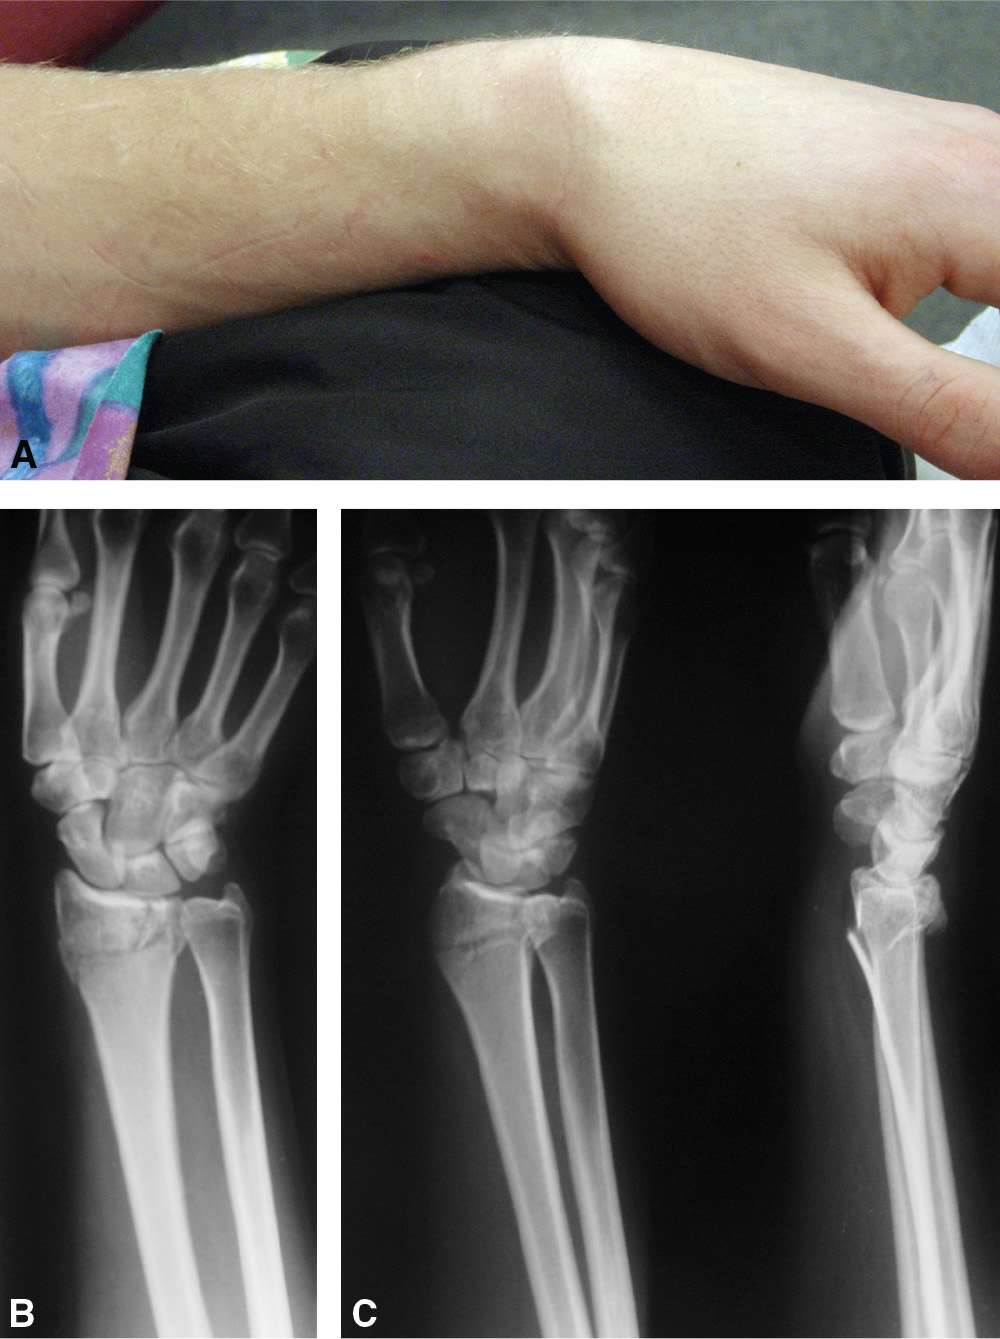

- Внешняя деформация руки.

В каждом отдельном случае точный перечень симптоматики и её интенсивность будет определяться индивидуально в зависимости от особенностей конкретной ситуации и полученной травмы. Но при этом обязательно следует обращаться за помощью к докторам. А также могут быть отягчающие факторы в виде смещения, проявления осколков, повреждения мягких тканей. Только доктор проведёт соответствующее обследование, поставит точный диагноз и составит дальнейший план лечения и реабилитации. Только при таком подходе можно достичь выздоровления и избежать многочисленных осложнений. А для скорейшего выздоровления в Минеральных Водах следует обращаться к специалистам частного центра реабилитации «Исток».